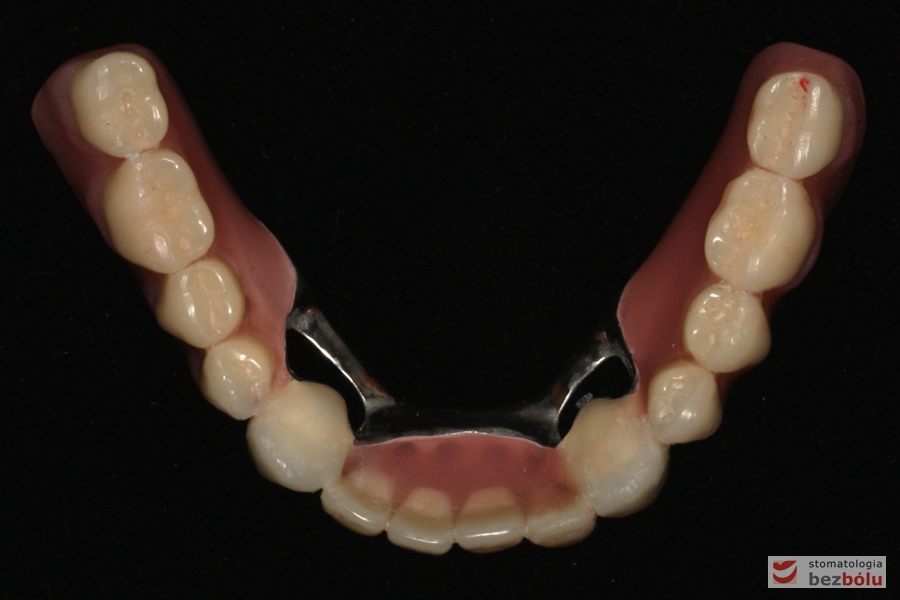

Odbudowa protetyczna żuchwy - wykonana przy użyciu zębów Michał Anioł Integrale

Odbudowa protetyczna żuchwy – wykonana przy użyciu zębów Michał Anioł Integrale